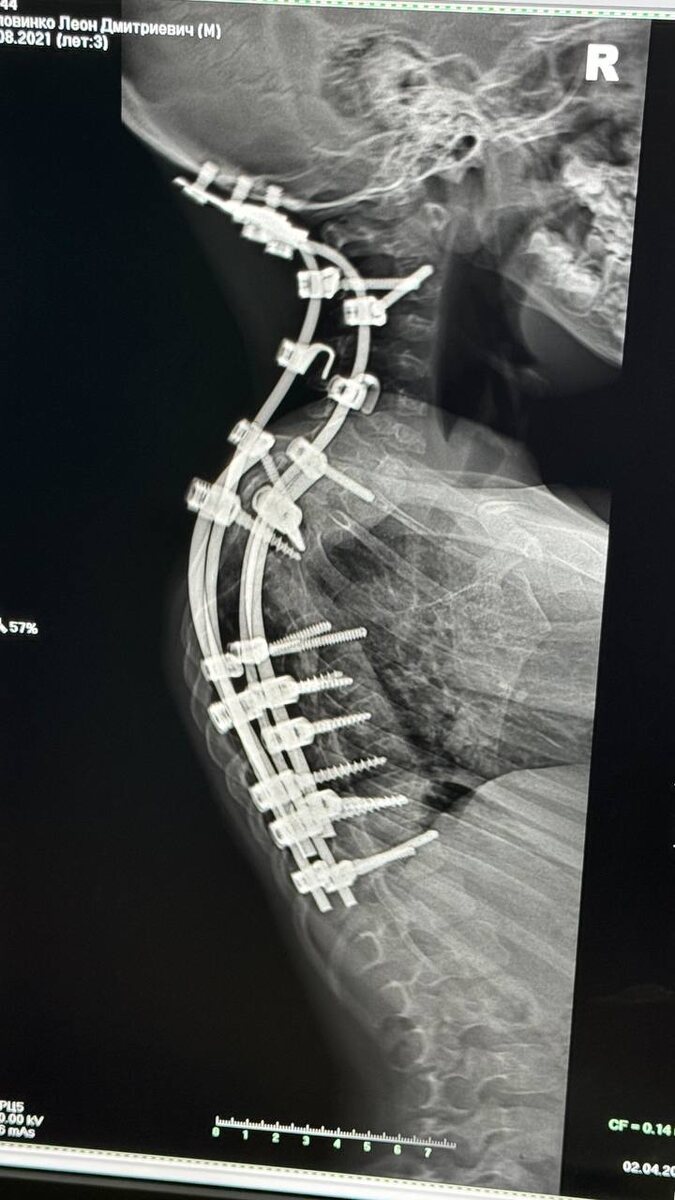

Сделали снимок🙏🏻 Отправила врачу в Москву и для МСЭ. Надеюсь, все на месте и как нужно🙏🏻🥲

Сделали снимок🙏🏻

Отправила врачу в Москву и для МСЭ.

Надеюсь, все на месте и как нужно🙏🏻🥲